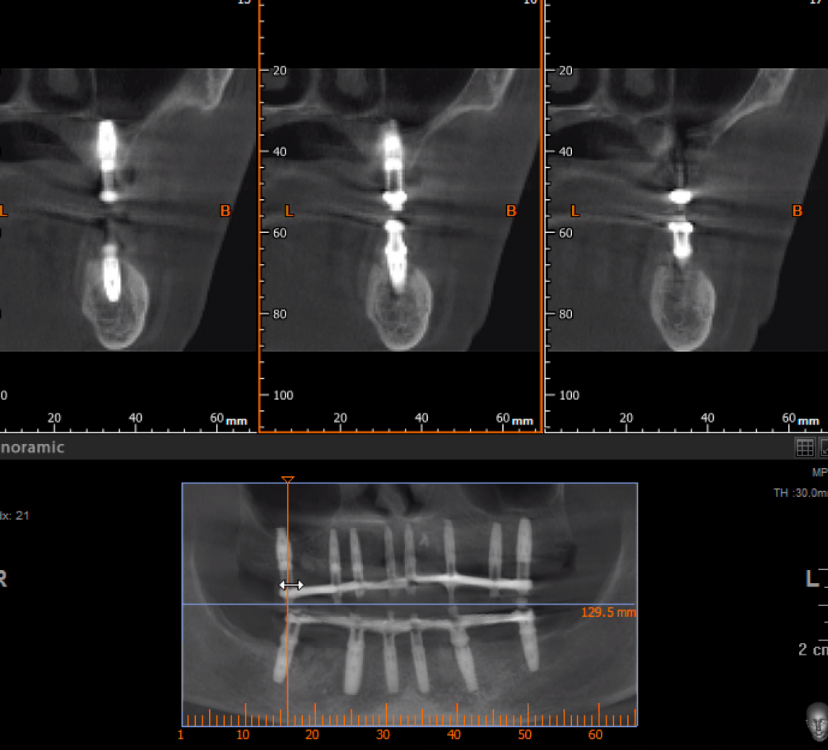

pit Опубликовано 29 ноября, 2021 Поделиться Опубликовано 29 ноября, 2021 (изменено) Планировал верх сделать из 4х сегментов, но не смог установить имплант в позицию 24 зуба- сломал гребень. Решил сделать в/ч подковой. Видео имплантации на н/челюсти здесь: https://youtu.be/T2__zlmJEm8 Изменено 29 ноября, 2021 пользователем pit 8 1 2 Ссылка на комментарий